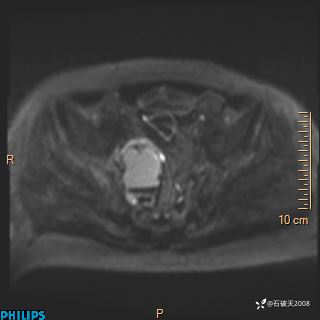

现病史:7个月前患者因骶尾部占位就诊于北京大学人民医院,MRI示:骶骨右侧及右骶前占位,考虑骨巨细胞瘤可能,动脉瘤样骨囊肿可能,神经源性肿瘤待排。行手术治疗,术后病理回示:XXXXX。术后给予对症治疗,具体不详,恢复良好。近几个月反复出现发热,伴骶尾部不适,多次住院给予对症治疗,2天前患者无明显诱因再次发热伴骶尾部不适,无大小便失禁,为求进一步治疗,遂门诊来我院,在门诊初步检查后,以“骶尾部肿物”为诊断收入我科。入院来患者神志清,精神一般,饮食睡眠可,大小便无明显异常,体重无下降。

2023年3月份MRI影像

增强轴位